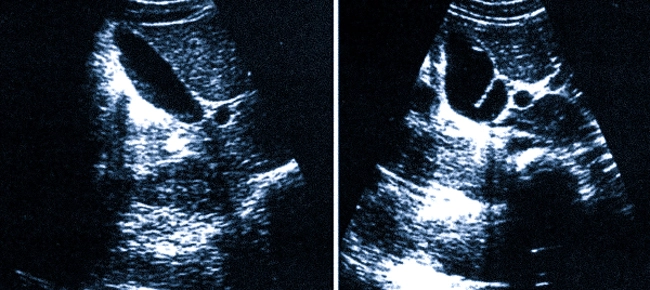

УЗИ брюшной полости — это надежный способ оценки состояния внутренних органов с применением ультразвуковых волн. Метод абсолютно безболезненный и не несет риска для здоровья пациента. Специалисты нашего медицинского центра проводят ультразвуковое исследование на аппаратах экспертного класса, которое обеспечивает точную диагностику широкого спектра патологий.

Во время УЗИ органов брюшной полости наши специалисты оценивают следующие анатомические структуры:

- Печень (структуру ткани, очаги воспаления, новообразования);

- Желчный пузырь (форму, размер, наличие камней и осадка);

- Поджелудочную железу (отек, изменение плотности паренхимы, воспалительные процессы);

- Сосуды (определение тромбоза, стенозов, нарушений кровотока).

Во время процедуры специалист оценивает:

- расположение;

- размеры;

- форму;

- контуры;

- структуру и эхогенность паренхимы;

- особенности сосудистой системы;

- влияние соседних структур на исследуемый орган и пр.